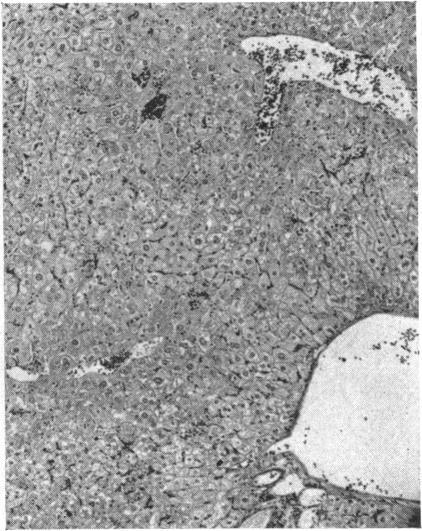

The relation between ammonia intoxication and liver disease is not clear. Ammonia appears to be relatively non-toxic to normal individuals, whereas some patients with liver disease appear to be exquisitely sensitive to dietary protein, ammonia-releasing substances, and ammonium salts. In an attempt to elucidate this relationship the intravenous LD(50) of ammonium chloride was determined in both normal mice and in those with liver disease produced by a variety of means. Parenchymal damage was created by acute and chronic carbon tetrachloride intoxication, a low-protein, lipotrope-deficient diet, and mouse hepatitis virus. Mice in which the portal vein had been partially ligated and those infected with Schistosoma mansoni developed portal-systemic collateral circulation. Groups of these mice were placed on high-protein diets and ammonia drinking water for periods as long as two months. A combination of both parenchymal damage and collateral circulation was induced in mice either by bile duct ligation or by a combination of schistosomiasis and acute carbon tetrachloride intoxication. When the above groups of mice with liver disease were compared with normal control mice in the same weight range, the LD(50) of ammonium chloride showed no striking change.

氨中毒与肝脏疾病之间的关系尚不清楚。氨对正常个体似乎相对无毒,而一些肝病患者似乎对膳食蛋白质、氨释放物质和铵盐极为敏感。为了阐明这种关系,测定了正常小鼠以及通过多种方式诱发肝病的小鼠静脉注射氯化铵的半数致死量(LD50)。通过急性和慢性四氯化碳中毒、低蛋白、缺乏促脂物质的饮食以及小鼠肝炎病毒造成实质损伤。门静脉部分结扎的小鼠以及感染曼氏血吸虫的小鼠形成了门体侧支循环。将这些小鼠分组,给予高蛋白饮食并饮用含氨的水,持续长达两个月。通过胆管结扎或血吸虫病与急性四氯化碳中毒相结合的方式,在小鼠中诱导实质损伤和侧支循环同时出现。当将上述患有肝病的小鼠组与相同体重范围的正常对照小鼠进行比较时,氯化铵的LD50没有显著变化。